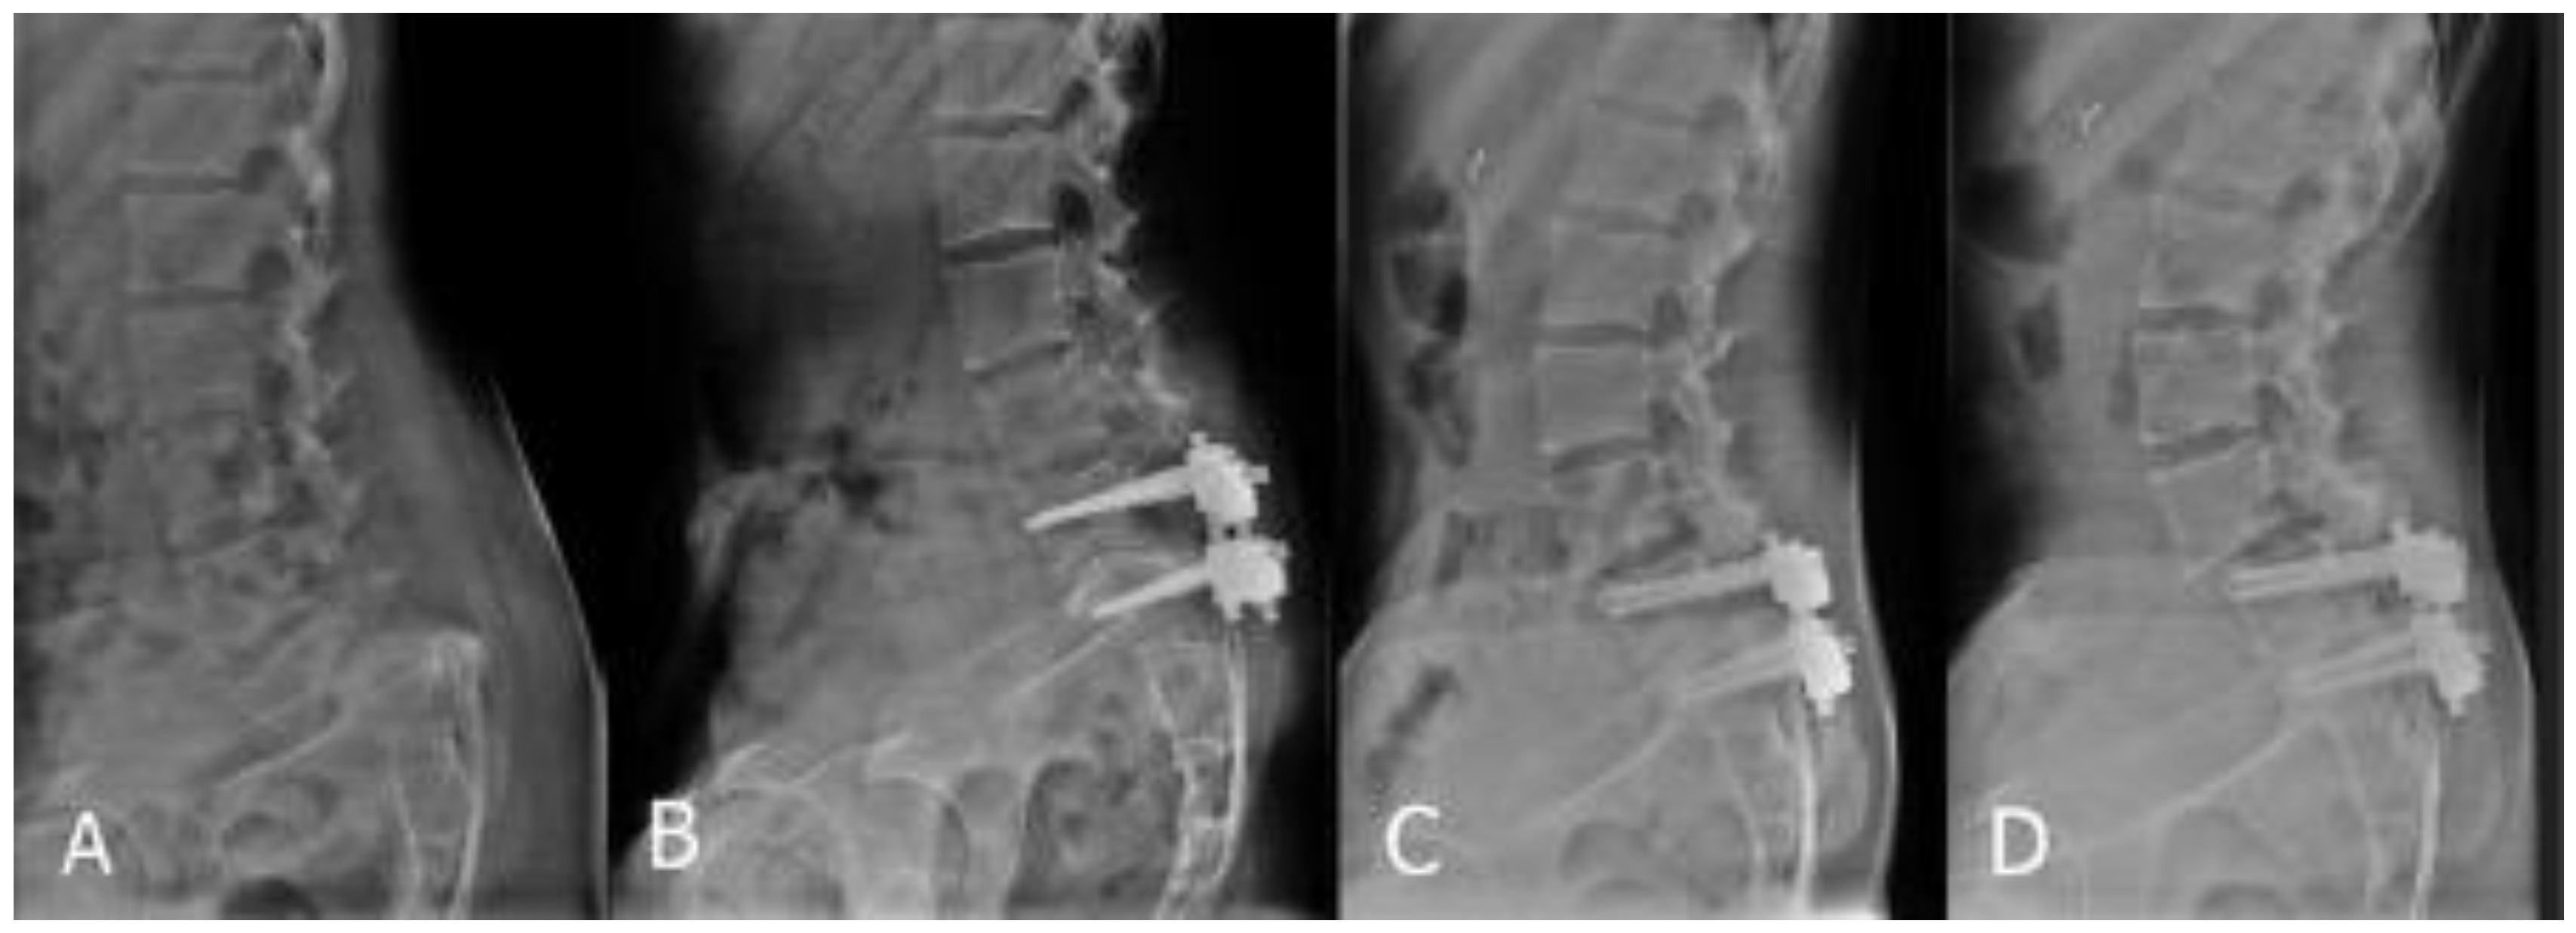

2.2. Surgical Technique

2.2.1. Posterior Approach Only

2.2.2. Combination of Posterior and Anterior Approaches

3.1. Slip Reduction and Retention